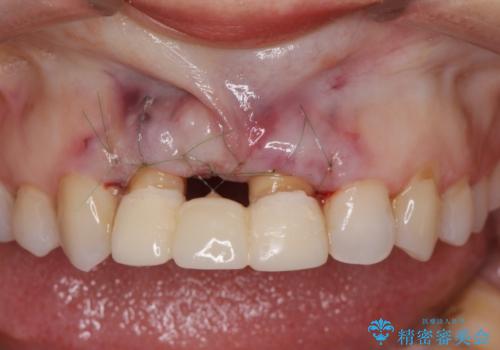

根管治療を行ったのち、歯周外科を行うことで、欠損部の歯ぐきの厚みを出し、縁上歯質を獲得することで、長期的な予後の見込めるブリッジを製作できる環境を整備していきます。

歯周外科をおこなったことで歯ぐきのラインを整え、脱離しないような前歯のブリッジを作製することができました。